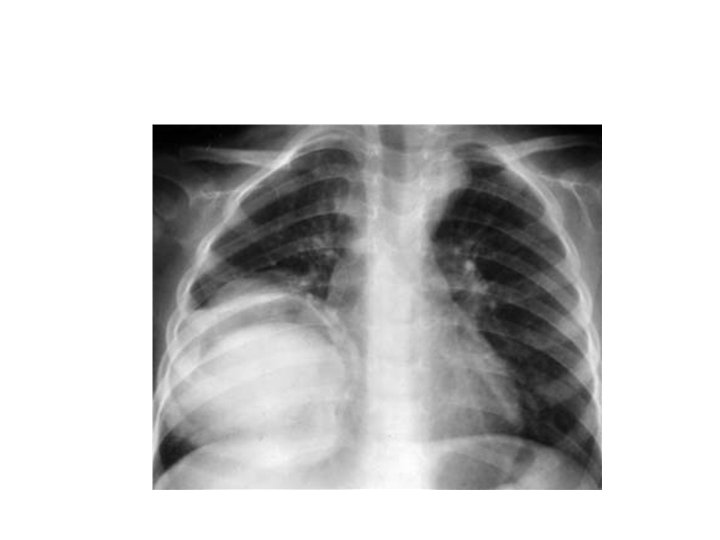

Kyste hydatique du poumon • Evolution radio-clinique 06 stades successifs: 1) Kyste sain. Asymptomatique de découverte fortuite (stade exclusivement radiologique)= opacité ronde, nettement limitée, en « boulet de canon » , dans un parenchyme sain, profil, opacité ovalaire « en ballon de rugby » , signe de NEMENOFF en radioscopie